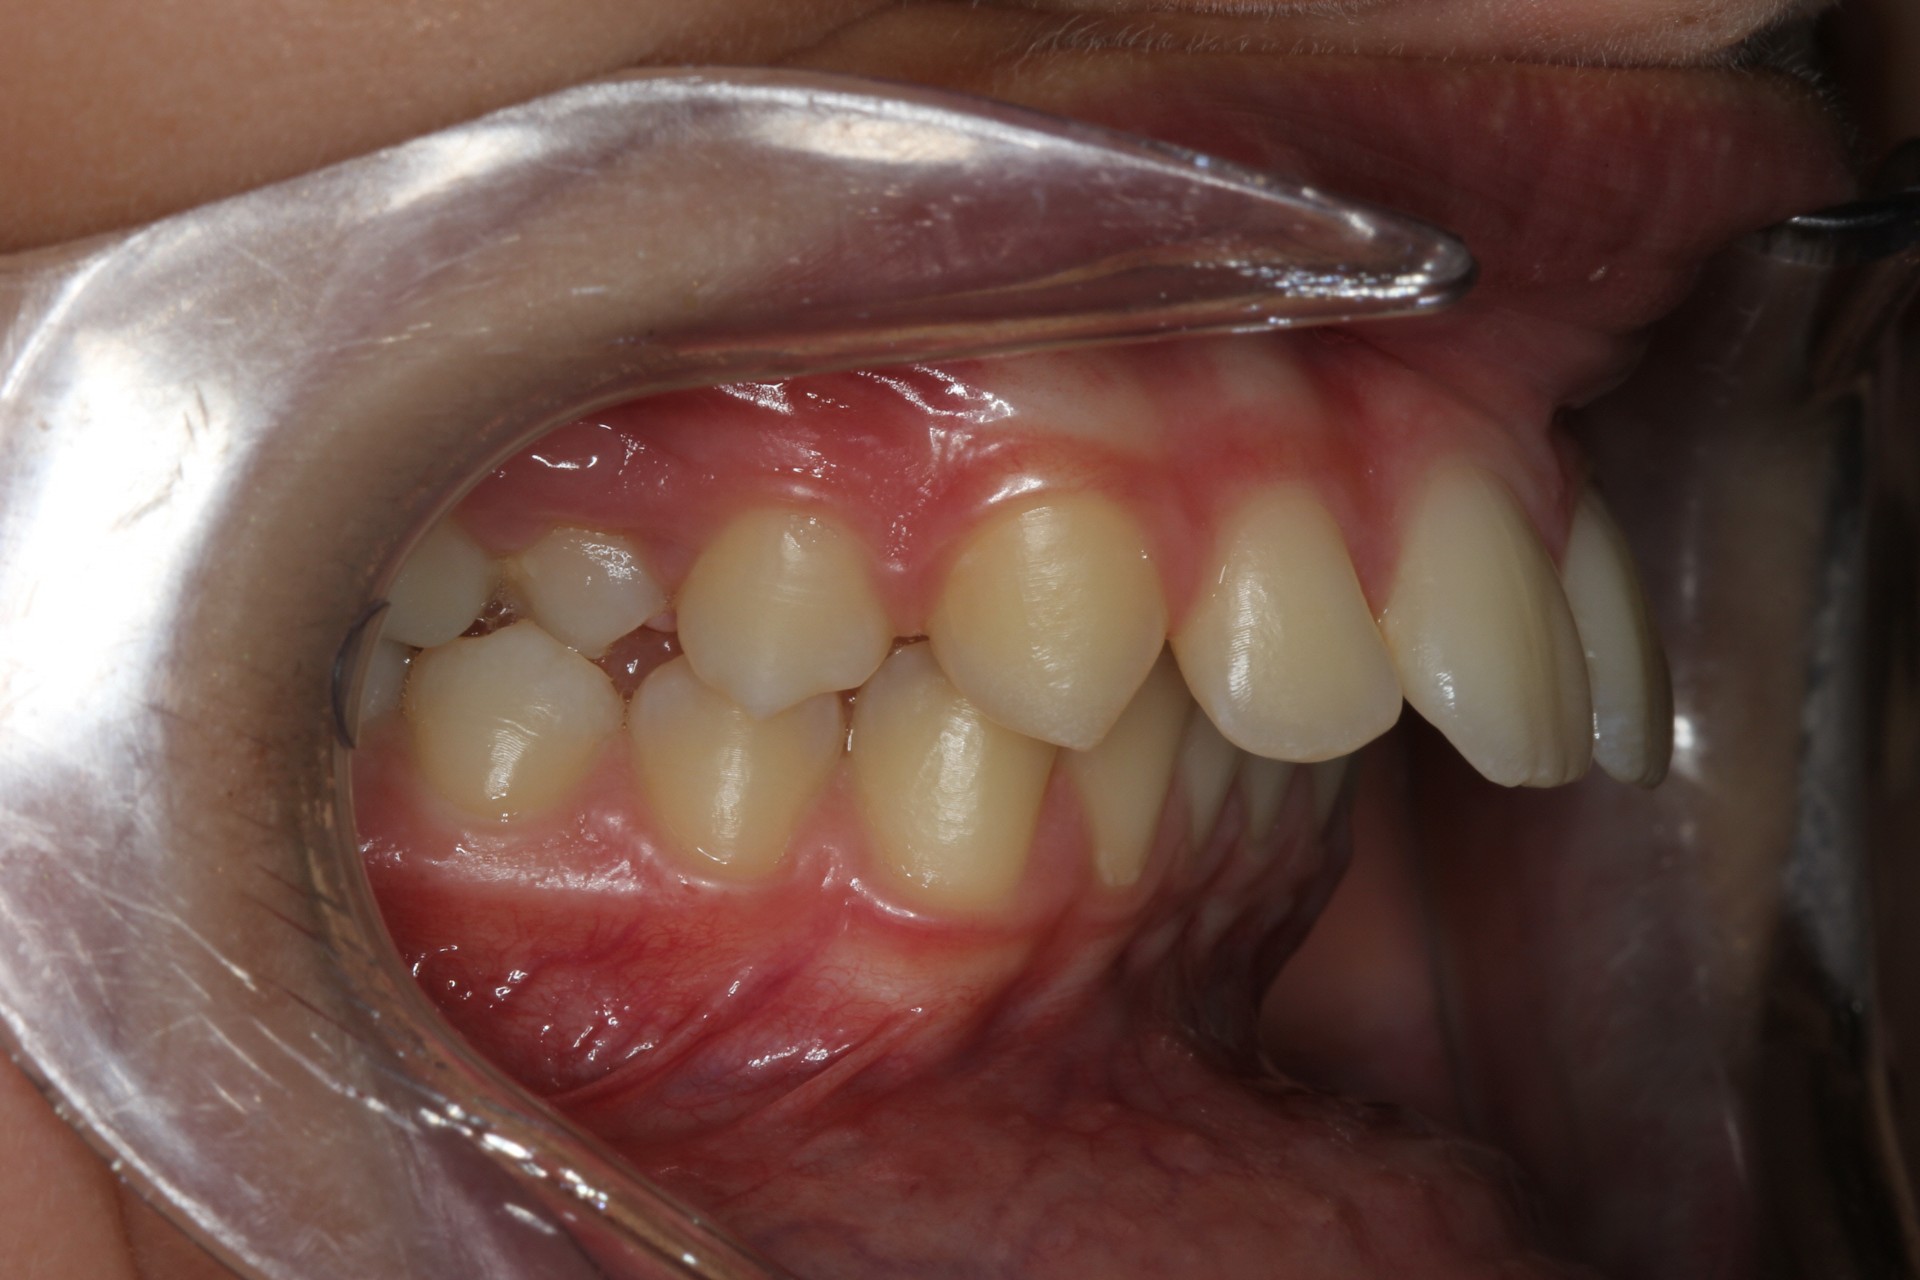

Protruding front teeth and spacing – Child case